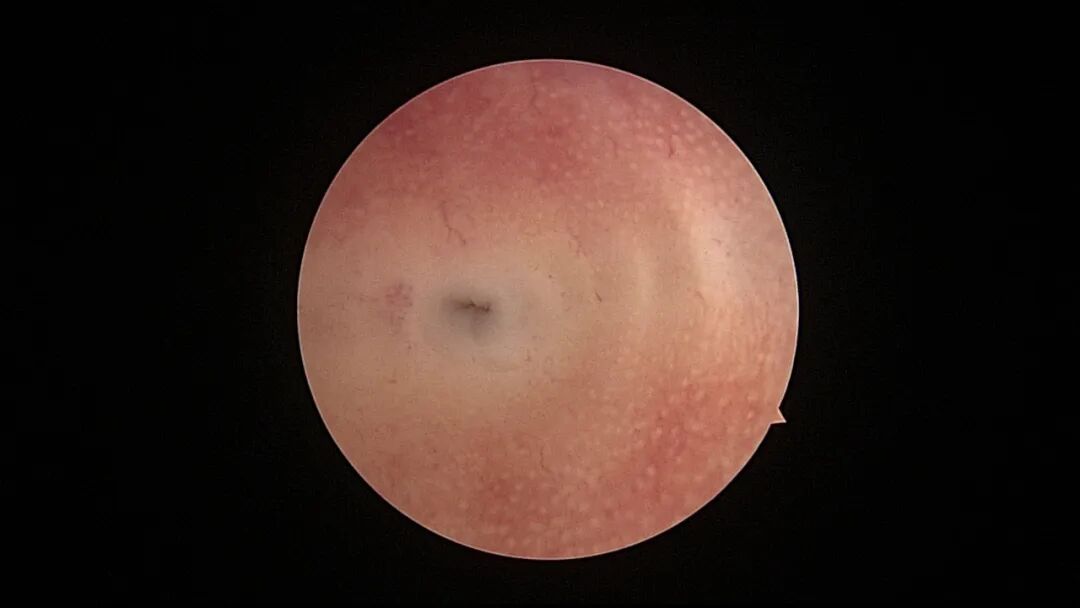

病例2:36岁,G4P2,剖宫产2次。异常子宫出血5年,主要为月经干净半个月左右少许出血,月经周期第14天B超内膜厚0.6cm(双层)。月经周期第18天宫腔镜探查,内膜平滑,见腺体开口,病检为增殖期样子宫内膜。